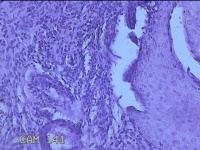

宫颈6点、12点组织

性别

女

年龄

39岁

临床诊断

人乳头瘤病毒感染

一般病史

宫颈筛查异常。

标本名称

大体所见

1.“宫颈6点组织”:灰白粉红色组织0.7x0.5x0.2cm一块。 2.“宫颈12点组织”:灰白暗红色组织 0.8x0.7x0.2cm一块。